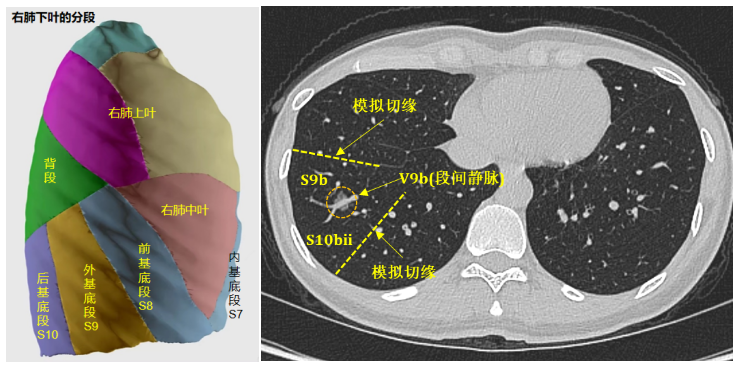

然而,患者右肺下叶结节位置特殊:结节处于肺实质深部,且刚好位于外基底段与后基底段交界区,段间静脉正好穿行于结节之间。此外,该患者的基底段各段发育不均,前、外基底段较小,而后基底段较大。由于结节位置深,不宜行局部楔形切除,若行肺段切除则无论切除哪一肺段均难以保证足够的安全切缘,若切除肺叶或者切除多个肺段,则会损失更多的健康肺组织,肺功能将受到影响。

如何保证足够的肿瘤学切缘,又为患者保留更多的健康肺组织,成为治疗组面临的一大难题,对外科医生手术方案设计和手术技术操作能力也是一种考验。刘成武副主任医师团队通过对患者的胸部CT影像进行仔细分析讨论发现,可以在完整切除本身就较小的外基底段的基础上,再切除后基底段的一个次亚段,这样的话,无需切除整个后基底段,即可实现足够安全的肿瘤学切缘,可为患者保留绝大部分后基底段组织。

一直以来,由于段门位置深、段结构变异多、需处理的段间交界面多等因素,基底段解剖性切除是解剖性肺段切除术中最具挑战性的,尤其是当涉及外基底段、甚至联合段/亚段/次亚段切除时难度更高,要想通过更微创的单孔胸腔镜手术完成更是难上加难。第一,所需切除的肺段及次亚段位于下肺正中央,需处理的解剖结构(动脉、静脉及支气管)均位于肺实质最深处,要想暴露最深面的S10bii次亚段结构,只有将肺完全劈开才有可能实现;第二,要把整个下肺劈开,必须先穿过密集分布着肺段血管/支气管的段门,在肺内打通一条“隧道”,而这通过传统单一入路根本无法实现;第三,建立“隧道”后,还需准确找到劈开界面并精准劈开,而不伤及需保留的肺组织;此外,靶肺与下叶肺各段均相接,需进行四个面的段间分割。

针对上述难题,在刘伦旭教授、蒲强教授的指导下,治疗团队最终设计了分别经肺裂及肺下韧带的“双入路”手术路径、经前外基底段之间行“肺劈裂”的手术策略、采用荧光显影及改良膨胀萎陷“双显示法”的综合手术方案,逐一突破各个手术难点。